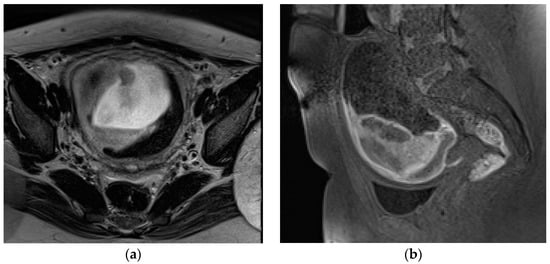

A collection of blood located anterior to the placenta between the chorionic membrane and the villous chorion and circumscribed from the umbilical cord is defined as preplacental or subamniotic hematoma (Figure 2).

Masselli et al. showed that MRI could be a useful tool for identifying PA, with high soft-tissue contrast, wide field of view, and excellent interobserver agreement [49]. The authors observed that the diffusion and T1-weighted images have higher sensitivity and diagnostic accuracy (sensitivity, 100% and 94%, respectively; diagnostic accuracy, 100% and 97%, respectively) than the T2-weighted half-Fourier RARE (sensitivity, 94%; diagnostic accuracy, 87%) and true FISP sequences (sensitivity, 79%; diagnostic accuracy 90%) in detecting hematomas. Moreover, according to changes in signal intensity of hemoglobin in placental tissue on T1 and T2WI, MRI is able to estimate the age of bleeding (Figure 3) [49].

Hyperacute hemorrhage is typically hyperintense on T2-weighted and DW images, being intermediate on T1-weighted images. Acute hemorrhage shows a drop of signal intensity on T2WI, resulting in a hyperintense T1WI. Subacute hemorrhage is hyperintense on T1WI due to the paramagnetic effect of methemoglobin. Chronic bleeding is hypointense on T1WI and T2WI. The finding of a hyperacute or acute placental hematoma should warn of the risk of progression to a higher degree of abruption, whereas subacute or late bleeding is usually stable [13,49,51]. Therefore, an accurate and timely diagnosis of PA and the prediction of its worsening are crucial when considering conservative treatment. A potentially unstable patient requires continuous monitoring and emergency preparedness. Since the diagnosis of PA is based on clinical features and not on imaging findings, MRI is not routinely performed; however, this method is extremely accurate for placental assessment, identifying the cause of second- and third-trimester uterine bleeding. MRI should therefore be considered after negative US, especially if the diagnosis of abruption could change management [13,54].